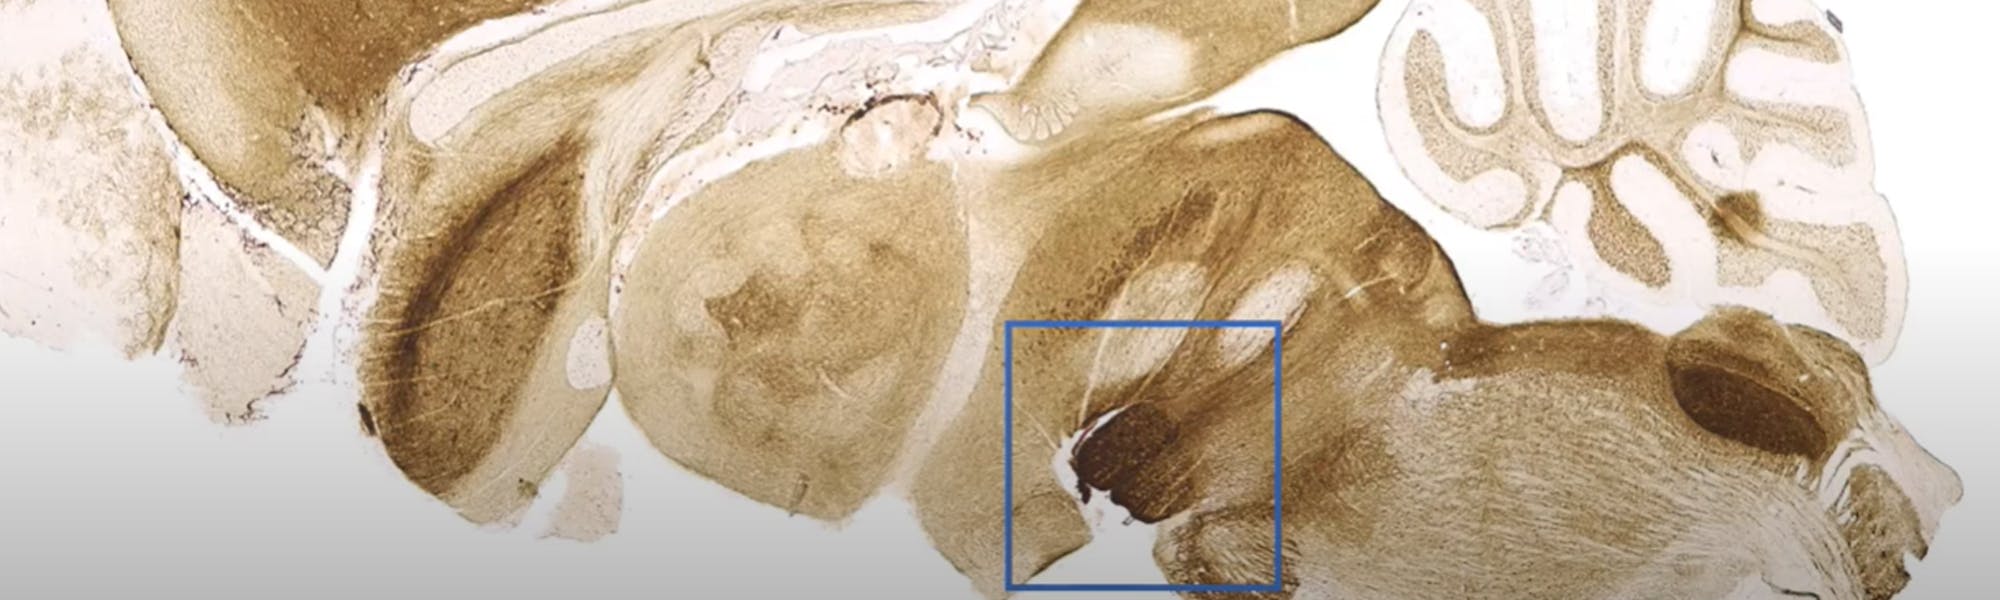

Banner image: Dr Junshi Wang from the Icahn School of Medicine at Mount Sinai